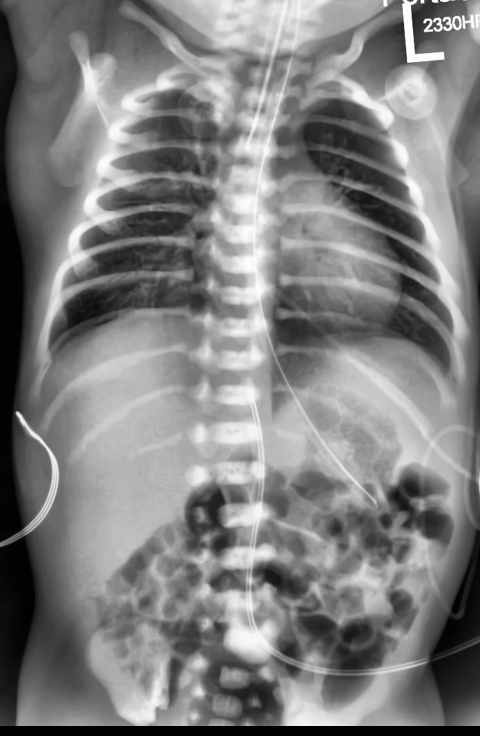

Automated catheter detection is a challenging task. Although most catheters have a radiopaque strip to facilitate detection, the strip may become less apparent depending on the projection angle. Catheters maybe confused by other similar linear structures like ECG leads and anatomy including ribs. Additionally, portions of catheters can be occluded by anatomical structures given that radiographs are a 2D projection of a 3D structure. For example, when a NGT is placed within the oesophagus, the catheter itself becomes less apparent due to the high density of the adjacent vertebrae. Finally, the number and type of catheters that could possibly appear in pediatric X-rays are unknown a priori. The catheters may be intertwined with each other thus making simple line tracing methods fail. Figure 1 gives three sample pediatric X-ray images with some common catheters highlighted in different colors.

To alleviate this annotation problem in catheter detection, we proposed to use X-ray images with simulated catheters by exploiting the fact that catheters are essentially tubular objects with various cross sectional profiles. To be more specific, a synthetic 2D projection of a catheter is generated by first simulating a horizontal catheter profile and then using it as a brush tip to draw along a B-spline path. This generated catheter is then composited with an X-ray image serving as the training data. Another contribution of this work is a segmentation network that can inherently take into account multi-scale information. This network adopts a UNet-style form and contains a recurrent module that can process inputs with increasing scales111Our code is available at https://github.com/xinario/catheter_detection.git.. We have empirically shown that by iterating through the scale space of the input image, higher recall is achieved as compared to using a single scale. Details about the methods are discussed in Section 3. Three sample detection results are shown in Figure 1.

The test dataset is collected locally and only contains frontal chest-abdominal X-rays from patients < 4 weeks old. This is the most common radiograph obtained to confirm placement of catheters such as UACs and UVCs in neonates. Currently, the test set has 35 fully labeled images with different catheter types with sample images previously shown in Figure 1. All the annotated catheters (lines excluding ECG leads) are treated as the same class in the detection.